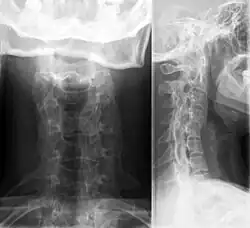

Im Langzeitverlauf tritt bei den chronisch progredienten Patienten häufig die Gelenkbeteiligung in den Vordergrund mit radiologisch nachweisbaren zerstörenden Veränderungen besonders an den Hüftgelenken. Neben allen großen Gelenken können auch die kleinen Gelenke betroffen sein. Eine lokale oder systemische Osteoporose kann durch die krankheitsbedingte Immobilität entstehen. Bei chronischer Beteiligung der Halswirbelsäule können die Wirbelkörper verschmelzen. Prognostisch besonders ungünstig ist die Kombination einer fortschreitenden Gelenksentzündung mit persistierenden systemischen Symptomen, anhaltenden Entzündungszeichen im Labor und Thrombozytenzahlen über 500/nl.

Häufig geht eine längere Phase mit Gedeihstörungen, Gewichtsverlust und subfebrilen Temperaturen über Monate der Diagnosestellung voraus. Die Gelenke weisen meist nur eine mäßiggradige Schwellung, Ergussbildung und geringgradige Überwärmung auf. Es zeigt sich jedoch oft eine ausgeprägte Bewegungseinschränkung mit bleibenden funktionellen Defiziten. Typischerweise sind die Handgelenke, Fingergelenke, Zehengelenke symmetrisch betroffen. Auch alle großen Gelenke können betroffen sein, ebenfalls die Kiefergelenke und die Halswirbelsäule.

Typischerweise bestehen Schmerzen an den Ansatzstellen der Achillessehne an der Ferse, an den Sehnenansätzen der Kniescheibe, dem Schienbein, an den Streckseiten der Extremitäten und am Becken bzw. tiefen Rücken. Diese sind nachts und in den frühen Morgenstunden sowie bei körperlicher Belastung besonders ausgeprägt und führen zu deutlichen funktionellen Beeinträchtigungen und Fehlhaltungen (Schonhaltung der Wirbelsäule mit Steilstellung der Lendenwirbelsäule und Rundrücken, Fehlbelastung des Fußes). Gelenkentzündungen treten zunächst vorwiegend an den Beinen auf mit asymmetrischem Befall großer und kleiner Gelenke. Nicht selten kommt es zur entzündlichen Veränderung eines ganzen Fußes. Häufig sind auch Schultern und Kiefergelenke mit betroffen. Die Beteiligung des Becken-Lendenwirbelüberganges und der Wirbelsäule wird meistens im Verlauf deutlich (Übergang in ankylosierende Spondylarthritis bzw. Morbus Bechterew). Ein ausschließlicher Befall der Wirbelsäule ist im Kindesalter sehr selten.